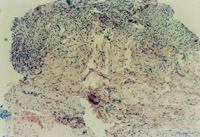

3-23 对其“皮点”进行组织学检查,该组织为从皮下组织中再生出的微血管、胶原组织、表皮细胞组织组成的再生皮肤组织团

3-24 该“皮点”逐渐扩展为皮肤组织团,各皮肤组织团互相融合